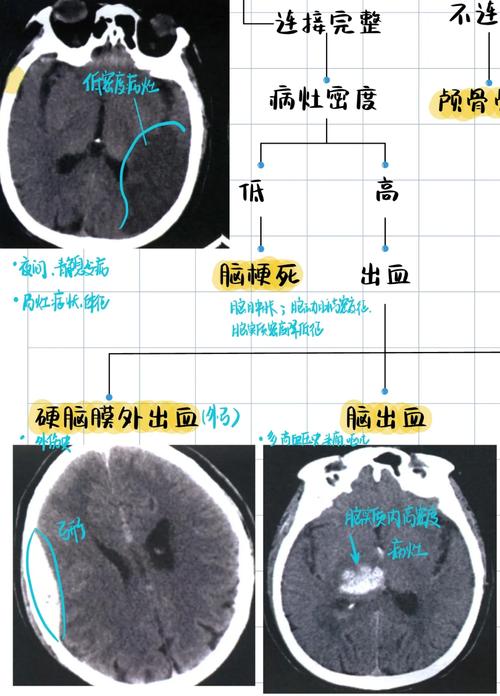

- CT表现:在发病最初的几个小时内,脑组织刚刚开始缺血,细胞水肿非常轻微,CT上可能完全看不出异常,这是CT检查的“盲区”。

- 唯一可能的早期迹象:如果堵塞的是大脑中动脉这样的大血管,CT上可能会出现“脑实质密度减低”或“脑沟消失”等间接征象,但这需要经验丰富的放射科医生才能发现,并且并非所有病例都会出现。

- CT表现:此时缺血区域的脑细胞开始死亡,细胞水肿加重,CT上开始出现低密度影,梗死的范围和形态会逐渐变得清晰,如果是在这个时间段之后做CT,就很可能发现异常。

- CT表现:坏死的脑组织会形成非常清晰的低密度灶,边界清楚,同时周围可能出现脑水肿,这个时期CT诊断脑梗的准确率非常高。

- 梗死灶太小:如果梗死的范围非常小(即所谓的“腔隙性脑梗死”),尤其是在脑干的深处,普通CT可能难以分辨,会被正常脑组织掩盖。

- 梗死灶位置特殊:某些部位的梗死,特别是小脑或脑干的梗死,在常规的头部CT平扫中可能不典型,容易漏诊。